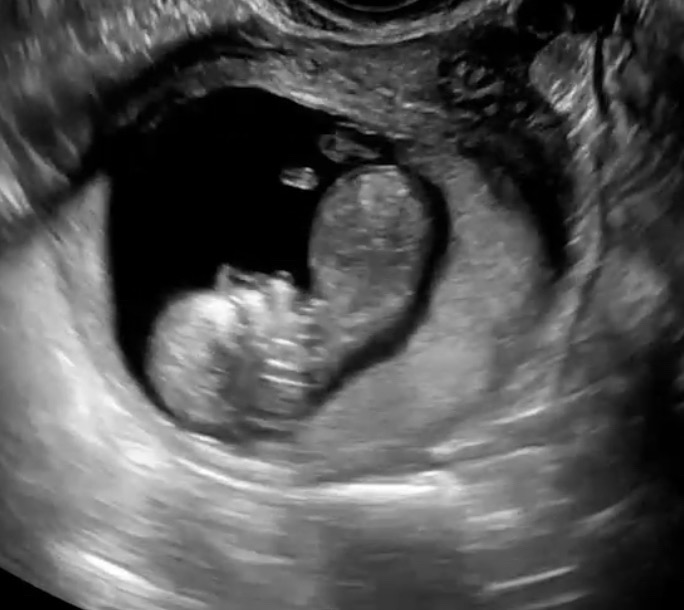

아가가 너무 머리가 아래긴한데.. 배쪽 튀어나온건 다리인데 아들일까여 딸일까여…🥹11주6일 사진이예엽!!

돌기가 안 보이는 사진이예요. ㅠ